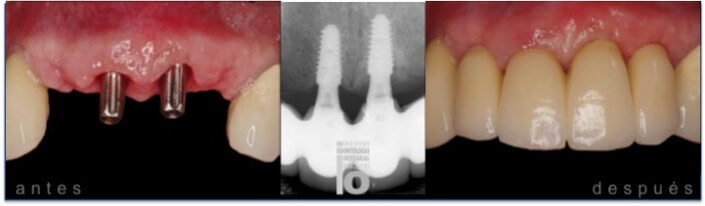

FRENTE ANTERIOR ESTÉTICO CON DOS IMPLANTES.